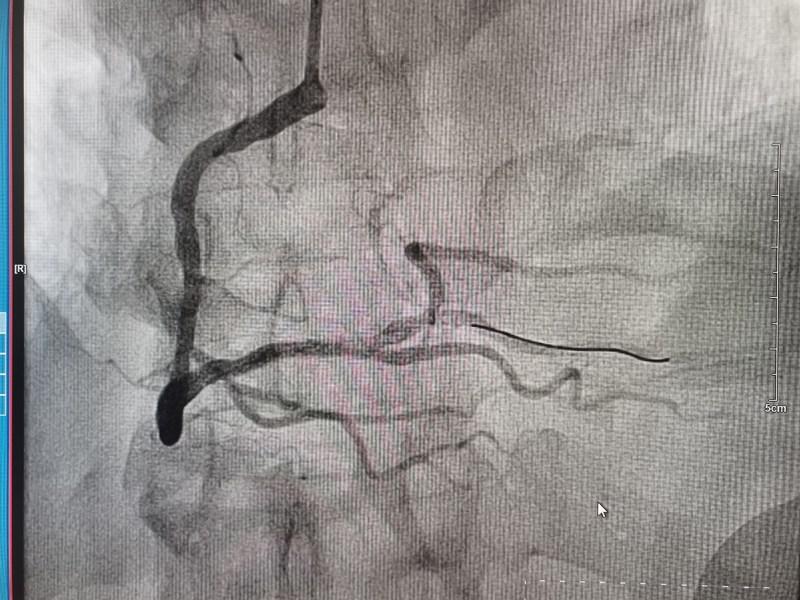

時間就是心肌,時間就是生命!一場生命的接力就此展開!心內(nèi)科團隊立即啟動胸痛綠色通道,電話通知導管室安排手術人員到位。董學濱副主任、汪韶君副主任醫(yī)師,以及導管室工作人員有條不紊地備好主動脈球囊反搏機、呼吸機等急診冠脈造影術前的各項準備工作,以及術中可能出現(xiàn)的各種突發(fā)狀況的應急預案。23:42分,造影手術正式開始,術中顯示裴某巨大的右冠狀動脈全程彌漫性病變,PLA近端完全閉塞。此時裴某生命體征極不穩(wěn)定,表情淡漠血壓低,隨時可能出現(xiàn)心臟驟停!治療承受著巨大的壓力和風險,心內(nèi)科團隊迎難而上,迅速將導絲通過閉塞血管,球囊擴張、打通閉塞的血管、植入支架,整個手術過程嫻熟、精準。隨著阻塞血管血流的恢復,裴某慢慢睜開了眼睛,神志恢復,胸痛癥狀消失,生命體征逐漸趨于平穩(wěn)。整個手術僅用時一小時。

術后